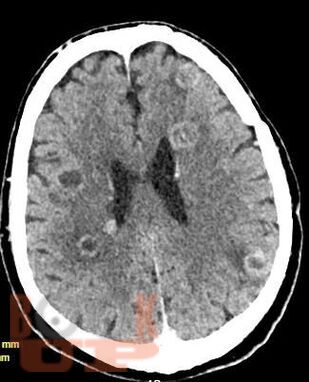

Учебное пособие освещает вопросы многоочагового поражения головного мозга. Рассматриваются различные нейрохирургические и неврологические заболевания с очагами поражения головного мозга в количестве более двух, такие как опухоли головного мозга (первичные и метастатические), воспалительные заболевания, демиелинизирующие заболевания, паразитарное поражение и другие патологии. В книге приведены алгоритмы дифференциальной диагностики данных заболеваний, начиная от особенностей клинической картины до специфики изменений сигнала в разных режимах МРТ. Также обозначена тактика ведения и прогноз заболеваний.